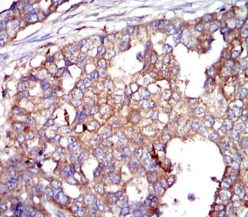

IHC    1/200 - 1/1000